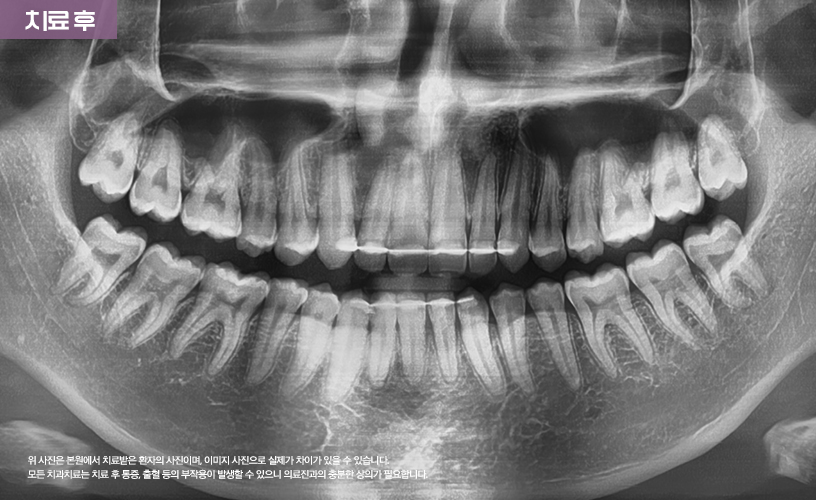

"투명교정 치료 사례"

상기 환자분은 상, 하악 앞니 벌어짐으로 인해

교정 치료를 고민하시다가 본 원에 내원하셨습니다.

본 원에서는 정밀한 검진을 통해 환자분의

앞니 벌어짐 상태를 점검한 다음

기존 일반적인 교정 치료 방식이 아닌

시스루 얼라이너 투명교정 치료가 수립되었습니다.

투명장치를 착용하여 치료가 진행되어

환자분의 일상생활에도 큰 지장을 주지 않으면서도

교정치료가 진행되기 때문에 환자분 역시

매우 만족해하셨습니다.